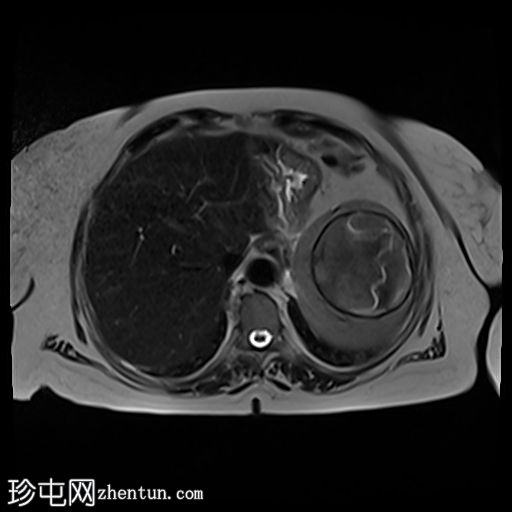

6.jpg

轴位

STIR序列

脾脏内可见一边界清晰的病变,T2加权像呈中等信号强度,边缘低信号提示钙化。病变内可见漂浮膜,呈棘球蚴囊肿特征性的蛇形征。

胆结石。